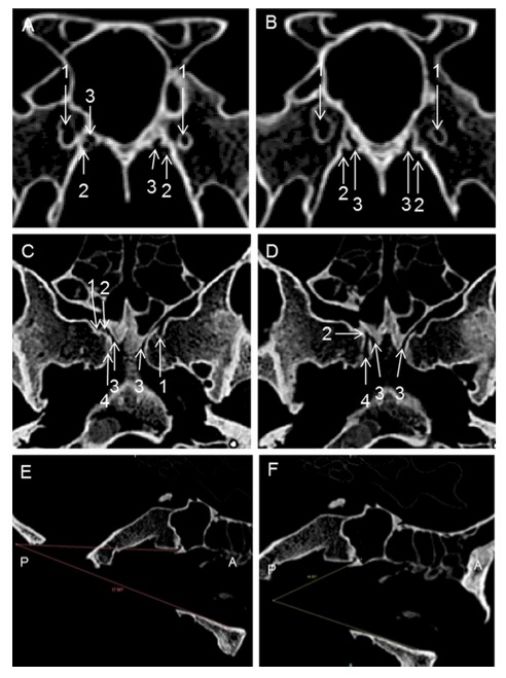

图示。0度镜观察。A、观察腭骨蝶突与蝶骨鞘突的关系;B、探针位于右侧腭鞘管内。注意腭鞘管后开口位于蝶骨鞘突前方;C、腭鞘管的下、内壁由腭骨蝶突构成,而上、外壁由蝶窦底围成;蝶骨鞘突恒定位于其鼻咽开口后方;B、D中蓝色虚线为蝶骨鞘突,红色虚线为腭骨蝶突,黄色虚线为蝶腭孔。Sphenopalat = Sphenopalatine; proc = process; Palatosphenoid = Palatosphenoidal.( 因此,作者认为蝶骨鞘突不参与构成腭鞘管,故更合适的命名应该为"蝶腭管")

图示。0度镜下新鲜尸头标本的左侧鼻腔解剖。A、暴露腭骨垂直板,注意蝶腭孔由腭骨蝶突和眶突围成;B、显露腭鞘管的鼻咽顶壁开口及其内穿行的上颌动脉的咽支。请留意翼腭窝内的腭鞘管开口;C、磨除腭鞘管前内侧壁(即部分腭骨蝶突)暴露管内容物,请留意其与蝶犁缝之间的联系;D、离断咽神经血管束并外推,可显露翼管开口。注意腭鞘管的上、外侧壁为蝶窦底壁,没有蝶骨鞘突的参与。在翼腭窝内,腭鞘管开口于翼管的内侧;E、从后往前磨除腭鞘管,暴露其外侧的翼管神经(F)。

图示。0度镜下右侧翼突进路的术中图片。A、磨除部分腭骨蝶突可见上颌动脉的咽支从翼腭窝向鼻咽顶壁走形;双极烧灼(B)并离断(C)咽神经血管束;D、外推翼腭窝内容物可以辨认翼突根部的翼管。同时可看到腭鞘管嵌入蝶骨。Pterygopalat = Pterygopalatine; Palatosphenoid = Palatosphenoidal.